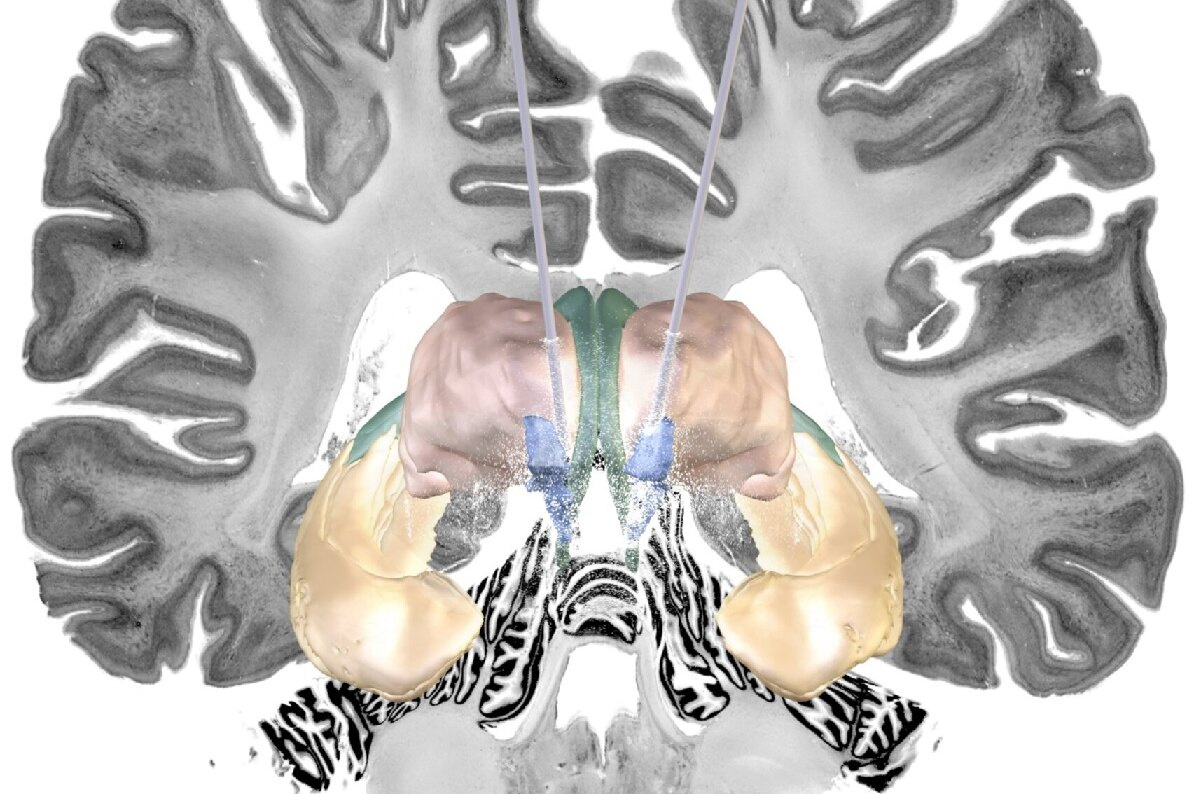

Группа исследователей из Медицинского университета Шаритэ, Берлин показала, что электрическая стимуляция определенной сети в мозгу пациентов с болезнью Альцгеймера приводит к ослаблению симптомов. Исследователи надеются, что полученные результаты проложат путь для дальнейших исследований и клинической практики.

Группа исследователей из Медицинского университета Шаритэ, Берлин показала, что стимуляция определенной сети в мозгу пациентов с болезнью Альцгеймера смягчает проявление симптомов.